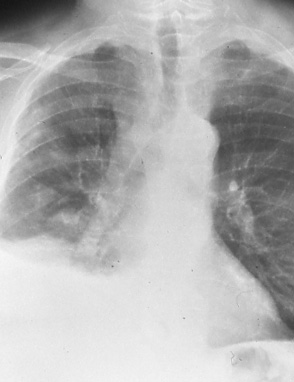

Stage IIIB

Fig. 48a: Posterior-anterior chest radiograph shows extensive mediastinal disease with compression of the right bronchus interrmedius and right hilar and mediastinal adenopathy. A moderately large pleural effusion is present, T4 N2 M0, stage IIIB.